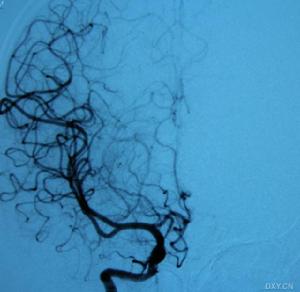

外傷後頸內動脈閉塞右側頸內動脈起始部閉塞

1、腦血管造影可見患側頸內動脈顱外段阻塞,大腦中與大腦前動脈影像消失。

診斷:對輕型腦損傷伴有頸內動脈閉塞的病人,常能從臨床表現與腦損傷程度不符而疑及此症,特別是傷後1~2天病情突然加重出現大腦半球缺血的徵象,如嗜睡、偏癱、偏身感覺障礙、患側眼黑矇或失語等症狀。若同時伴有一側頸動脈搏動減弱或消失,病側眼底動脈壓下降、蒼白變細或視網膜染色遲緩即應考慮本病。對重型腦損傷伴有頸內動脈閉塞的病人,要在腦缺血尚未至不可逆損害之前就明確診斷,並非易事,只有在密切觀察的前提下,及時採用影像學輔助檢查,才能作出早期診斷。腦血管造影檢查可以直接顯示動脈閉塞的具體部位和程度,有助於治療的抉擇可謂最有價值的診斷方法。CT和MRI檢查有助於診斷。